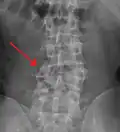

A burst fracture is a type of traumatic spinal injury in which a vertebra breaks from a high-energy axial load (e.g., traffic collisions or falls from a great height or high speed, and some kinds of seizures), with shards of vertebra penetrating surrounding tissues and sometimes the spinal canal.[1] The burst fracture is categorized by the "severity of the deformity, the severity of (spinal) canal compromise, the degree of loss of vertebral body height, and the degree of neurologic deficit."[2] Burst fractures are considered more severe than compression fractures because long-term neurological damage can follow. The neurologic deficits can reach their full extent immediately, or can progress for a prolonged time.

Diagnosis is by medical imaging.

Immediate hospitalization is required, as such injuries may result in varying degrees of spinal cord injury with possible paralysis. X-rays and MRIs are taken to determine whether the burst fracture can be managed with or without surgery.[3] Surgical management is required when the burst fracture is unstable. Predicting spinal instability of vertebral thoracic lumbar fractures is based on several radiologic and clinical parameters. Efforts to refine fracture classification schemes to better predict instability continue. Application of axial zone model proposed by physicians at Barrow Neurological Institute may enhance the ability to predict stability, depending not only on the number of columns, but also on the number of zones involved in the injuries. Further clinical and biomechanical studies are warranted to validate this model.[4]